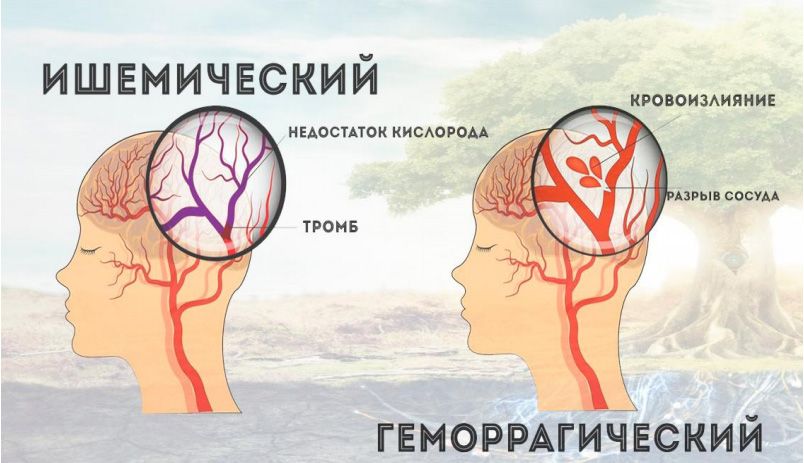

Ишемический инсульт левой стороны: симптомы и реабилитация